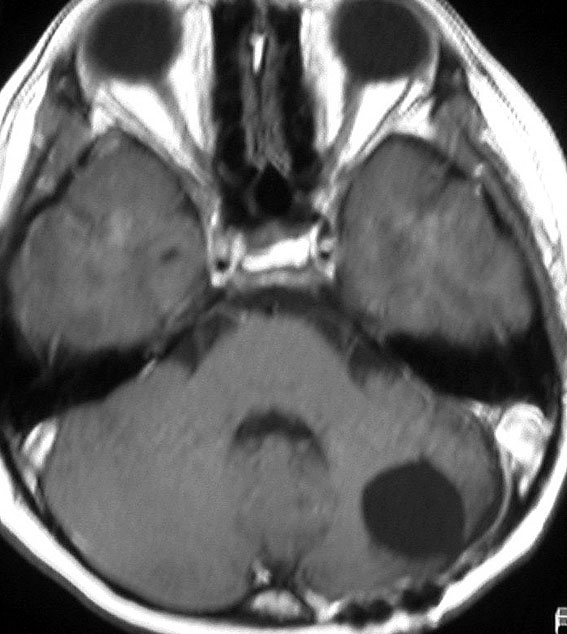

この例は,小脳半球にできたものです。のう胞(水たまり)を形成しています。髄芽腫の大きな特徴は,造影剤を入れないCT(左側)で腫瘍が少し白く見えることです(灰白質より高密度といいます)。細胞密度が高いので高密度になります。この例はclassic medulloblastomaですが,MIB-1は45%に達するもので,急激な腫瘍発育を示します。